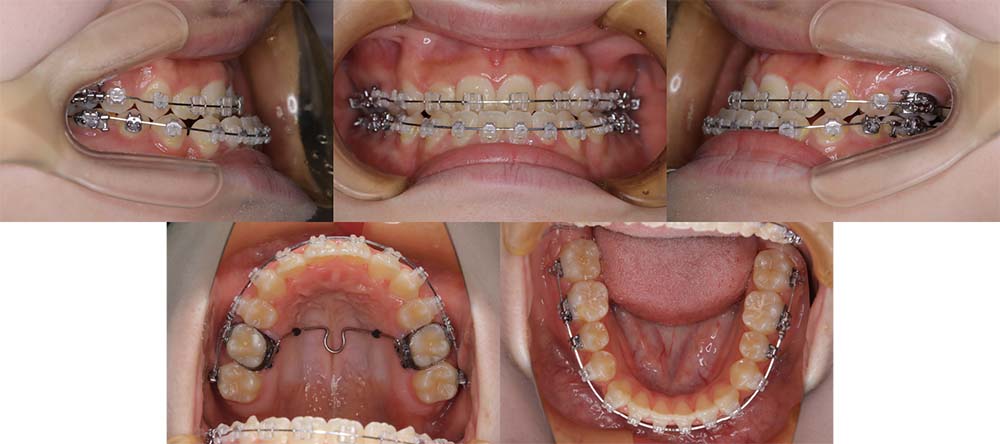

| 症例分類 | 顎変形症、叢生、側方偏移 |

| 診断名 | 下顎右側偏移を伴う上下叢生 |

| 主訴 | 歯並びがガタガタ、顎が右にずれている |

|---|---|

| 年齢 | 25歳4ヶ月 |

| 性別 | 女性 |

| 抜歯部位 | 上の左右第一小臼歯 |

| 使用装置 | 表側のワイヤー装置+外科矯正(手術を併用した治療) |

| 治療期間 | 2年1ヶ月 |

| 保定装置 | 固定式保定装置、取り外し式保定装置(8時間) |

| 費用 |

保険適応 [検査・診断等] 2万円程度 [装置装着] 5〜7万円程度 [調整料] 2,000〜7,000円程度/回 [手術前検査等] 2万円程度 [保定装置等] 4万円程度 合計18〜25万円程度 |

下顎の右側に偏移があり、骨格的にも受け口だったため、上顎両側第一小臼歯を抜去して、上下顎の手術を併用して治療を行いました。術前は前歯が反対のかみ合わせになり、初診時より咬合、顔貌は一旦悪くなります。術前矯正を1年7ヶ月した後に手術を行いました。

術後の顎間ゴムをしっかりと使用していただけたため、術後7ヶ月で治療が終了することができました。また、顎の歪みが残っていたため矯正治療終了後におとがい形成術をして、下顎の偏移を改善しました。

顎の歪みも下顎の前方感も改善することができ、上下のかみ合わせもしっかりと咬合することができました。